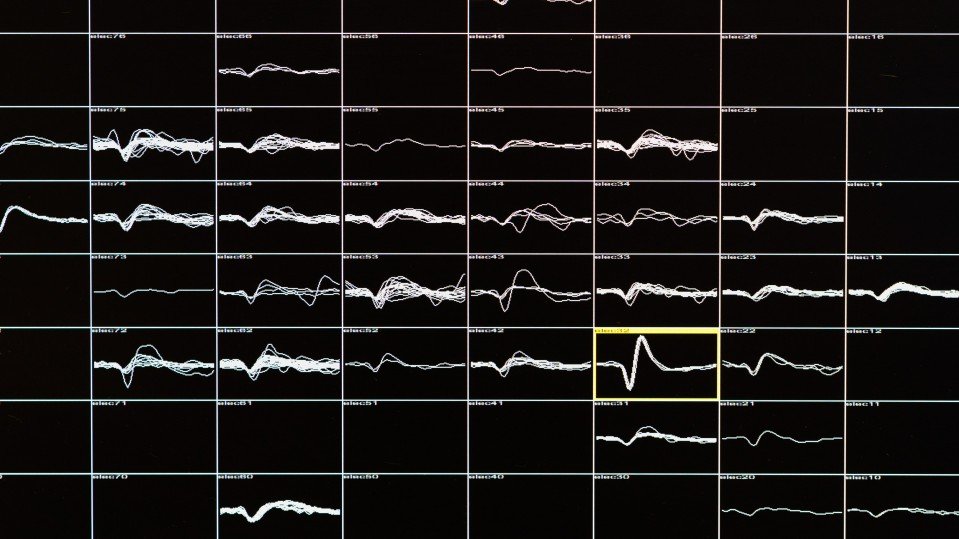

戈麦斯大脑的电信号,每个格子代表一个电极,格子中弯弯曲曲的线条,显示的是来自神经元的信号